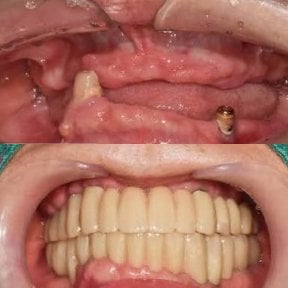

4. Full-mouth dental implants (All-on-4 / All-on-6)

For patients who’ve lost most or all of their natural teeth, Korean clinics offer full-arch restorations. These involve placing 4 or 6 implants to support a fixed arch of prosthetic teeth. It’s a stable, long-term alternative to removable dentures.

- Check reviews and patient photos. Look for real before-and-after cases and feedback from international patients.